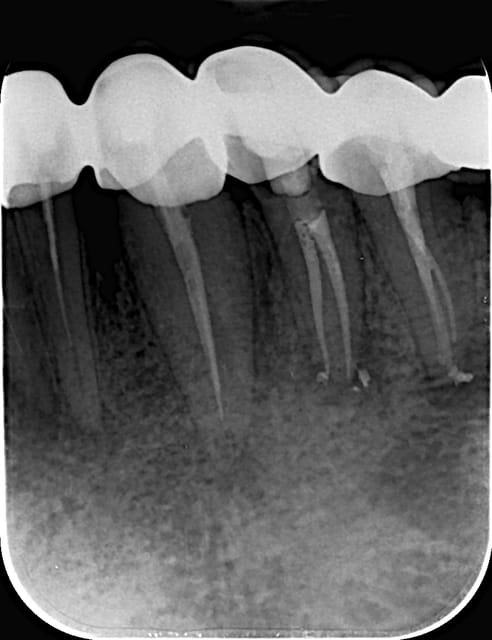

Bonjour a tout !

Initial e après obturation